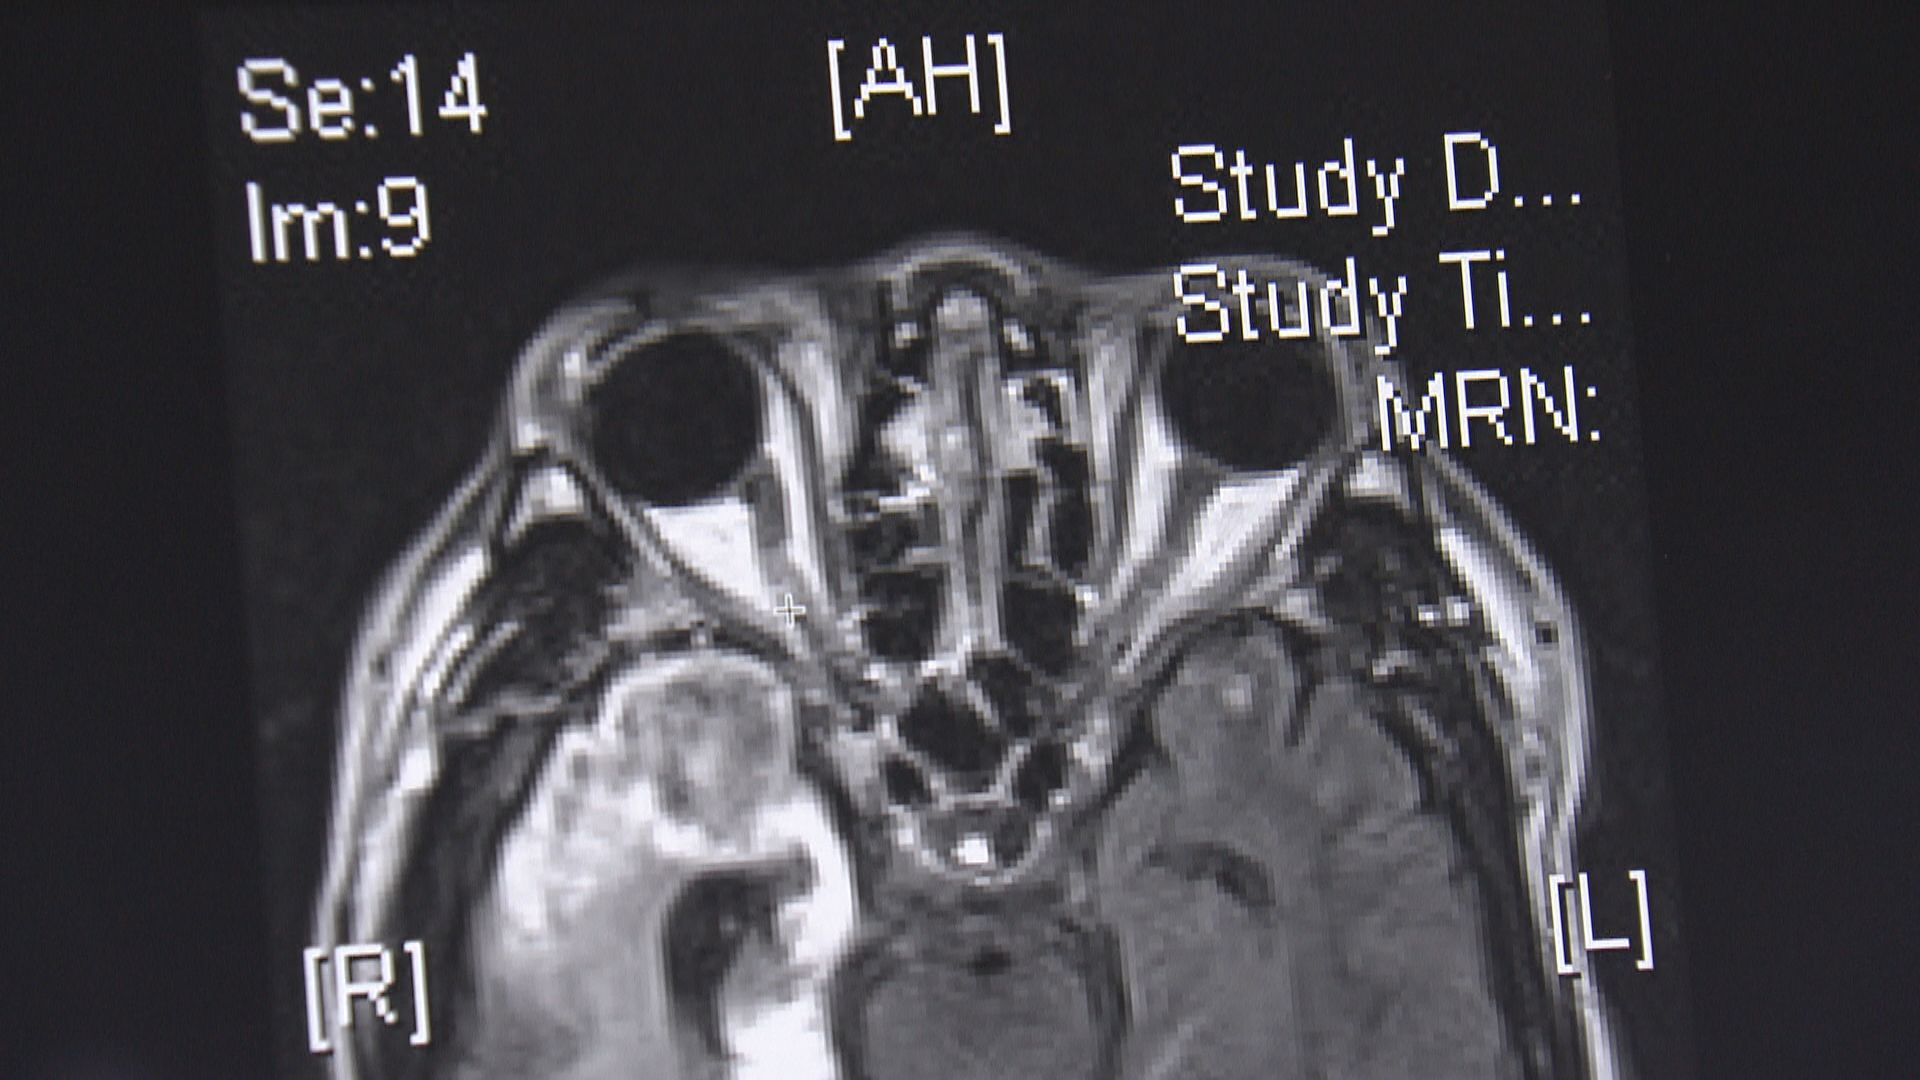

【Now新聞台】家衡是一位健身教練,平日經常要舉重,又要蹲低起身指導學員,腰部因而長期受壓導致椎間盤突出。到底經常做粗重工作的人士是否特別容易患上椎間盤突出?這個痛症又有多困擾病人?今集《杏林在線》有家衡分享病情,亦有中西醫講解不同治療方案。